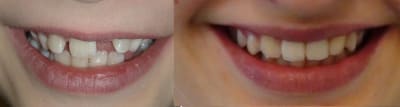

La 22 est centrée mais trop basse (image de gauche) ;

Elle est ingressée (image centrale) ;

Premier maquillage de 22 par adjonction de composite pour la faire ressembler un peu plus à une incisive centrale (image de droite).

Seconde séance de maquillages : retouche des canines et du bord cervical de 22